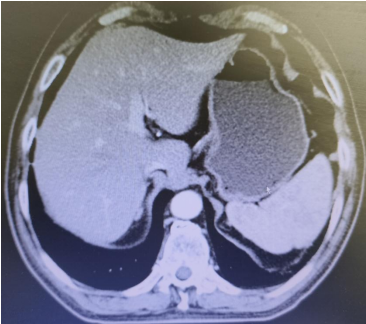

Abdominal CT films from March 3, 2020 (2 images)